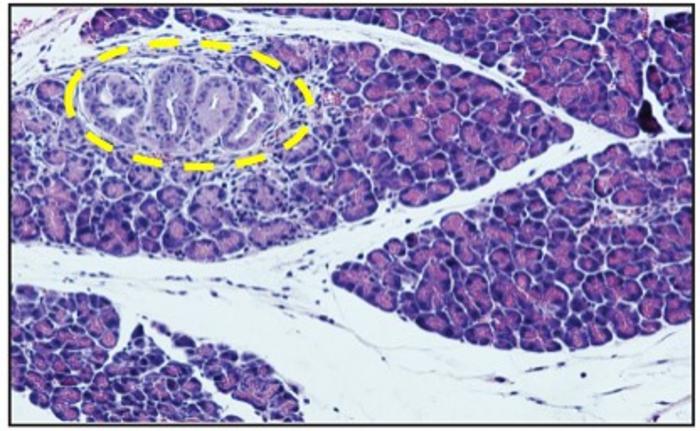

Their research entailed a comprehensive examination of P. gingivalis translocation from the oral cavity to the pancreas using mouse models. By introducing the bacterium to genetically engineered mice predisposed to PDAC, the team uncovered compelling evidence of accelerated cancer development.

Key findings from the study indicate that viable P. gingivalis was found in the pancreas of healthy mice after applying it to the gums, and prolonged exposure caused changes in the pancreas, affecting its microbial balance. Additionally, applying P. gingivalis orally sped up the progression from early pancreatic abnormalities to pancreatic cancer in mice with a specific genetic mutation. The research also showed that this genetic mutation helped P. gingivalis survive inside cells, and the bacteria supported the survival of pancreatic cancer cells even when conditions were tough. Prof. Nussbaum and his team's discoveries emphasize a direct link between P. gingivalis and the development of pancreatic cancer in mice, offering significant insights into how this disease progresses.